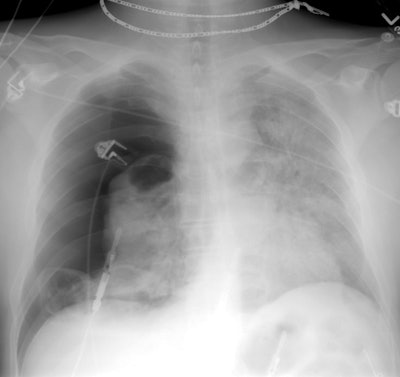

PCP with pneumothorax:

This is another example of pneumocytis pneumonia in a patient with cystic changes and a penumothorax. Extensive air space consolidation is seen in the left lung. CT (below) demonstrated the large right pneumothorax and the presence of areas of ground-glass attenuation. Interlobular reticulation within the areas of ground-glass reflects interstitial and interlobular septal infiltration by mononuclear cells and edema. This is often the predominant finding during the sub-acute phase of the illness. Thin walled cystic spaces are seen bilaterally. A thick walled cyst with an air-fluid layer is seen within the left lung.